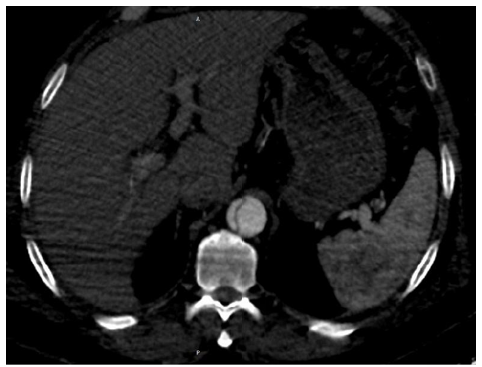

Case Report

Stanford Type A Aortic Dissection Complicated by Rupture in to the Pericardium a Case Report